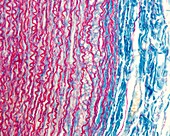

13613516 - Vein adventitia, light micrograph